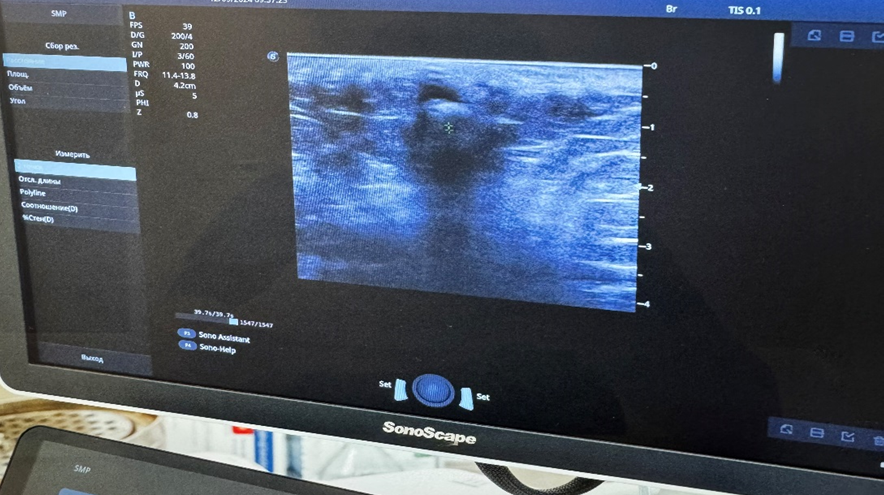

В качестве инструментального метода было проведено ультразвуковое исследование (УЗИ) инфильтрата на аппарате SonoScape S50 Elite (рис. 1) с оценкой состояния мягких тканей межьягодичной складки, эхогенность образования, его расположение, размеры, форму и структуру. Изучены лабораторные показатели: общеклинические анализы крови, мочи, биохимический анализ крови, коагулограмма.

Рис. 1. Аппарат SonoScape S50 Elite. Диапазон рабочих частот: 1–17 МГц

Fig. 1. SonoScape S50 Elite. Operating frequency range: 1–17 MHz

Учитывая наличие хронического воспаления у пациентов с ЭКХ, было проведено ультразвуковое исследование. На рис. 4 представлено ультразвуковое изображения пациента К., 52 лет. В подкожно-жировой клетчатке визуализируется мешковидное анаэхогенное образование размером 1,2×1,8×2,4 см на уровне Со3-Со4 с четкими контурами, а также анаэхогенное образование мешковидной формы 1,0×1,4×2,0 см неоднородной гетерогенной структуры на уровне S6-Со4, которые соединены между собой трубчатой структурой.

Рис. 4. Ультразвуковое изображение ЭКХ у пациента К., 52 года

Fig. 4. Ultrasound image of pilonidal sinus in patient K., 52 years old